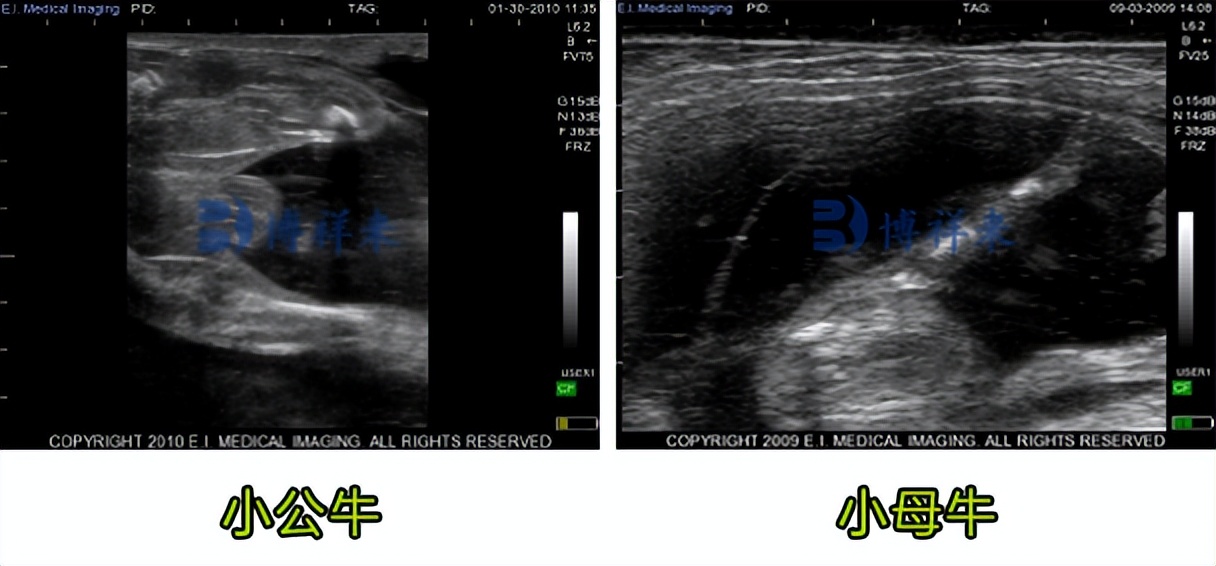

兽用B超可以检测小牛公母

可以通过实时超声对牛胎儿的雄性和雌性特征进行可视化的早期报告之一。在母牛妊娠第 70 天和第 120 天之间,准确率为 94%。在第 60 天之后可以进行准确的公母检测。测公母适合单胎动物,多胎动物会影响准确率。

牛用B超机检测小牛公母